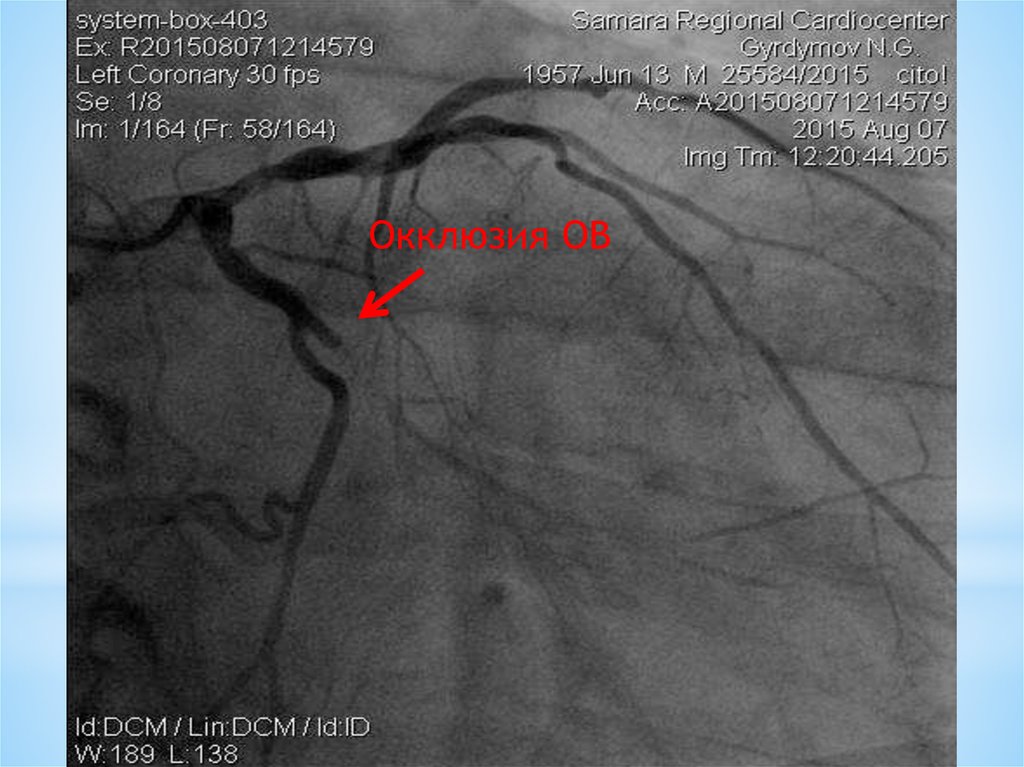

Окклюзия ОВ